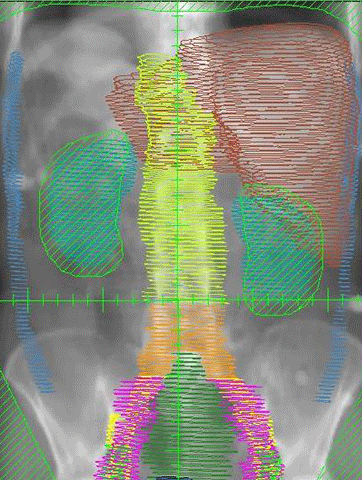

本日、米国食品医薬品局(FDA)は、ソマトスタチン受容体を発現する膵神経内分泌腫瘍(PNET)を含む消化管神経内分泌腫瘍(GEP-NET)の治療のためのルテチウム-177標識ソマトスタチンアナログ(Lu-177-DOTA-TATE)注射液(商品名ルタテラLutathera®)を承認した。欧州28か国では昨年2017年10月3日にすでに承認されていた。